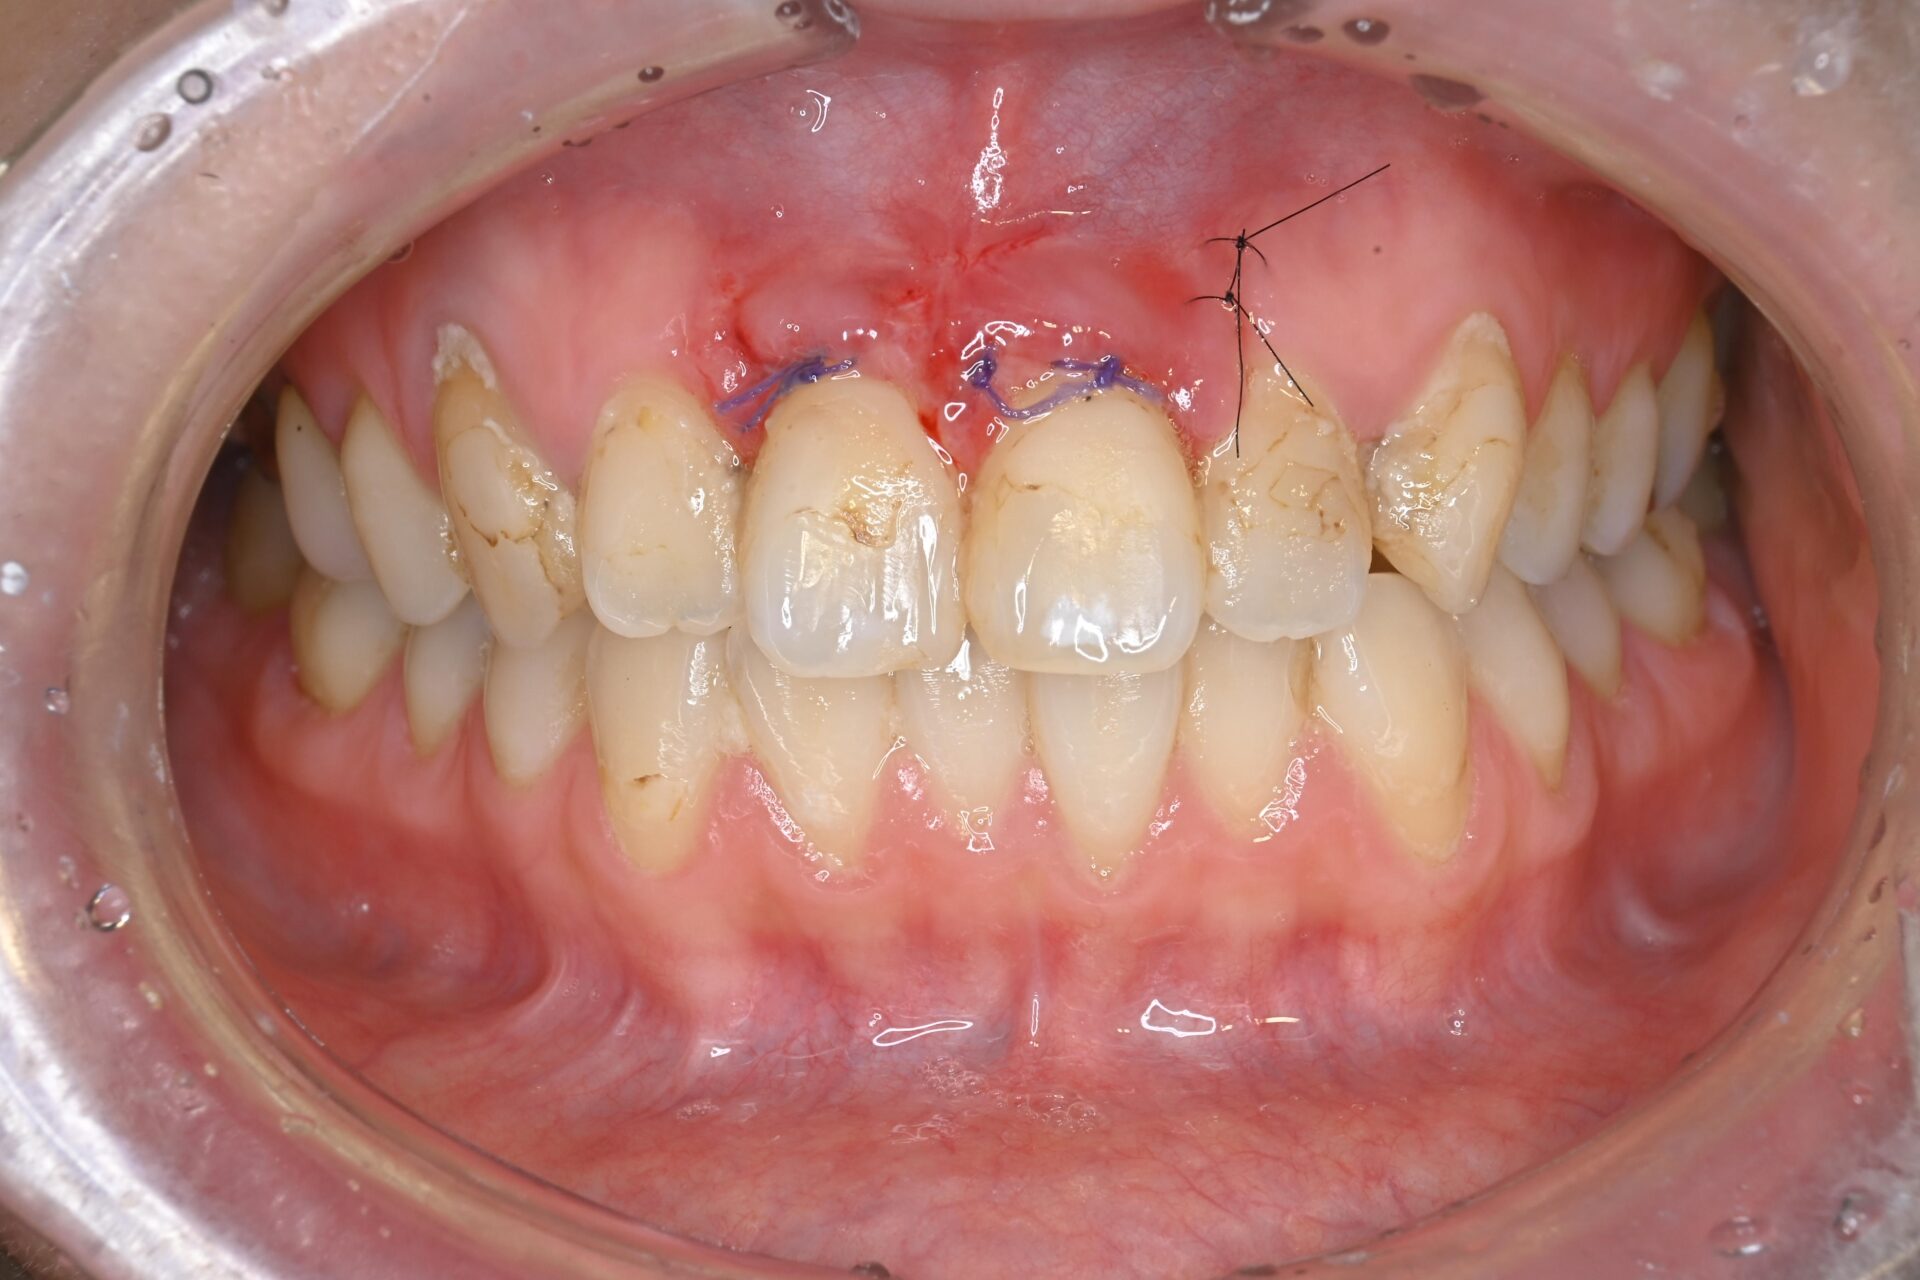

CTG(結合組織移植術) 臨床例①

前歯部の歯肉が薄く、付着歯肉が不足しているため、ブラッシングによる清掃が難しく炎症を繰り返していました。審美的にも不均衡が見られ、長期的な歯周組織の安定には改善が必要な状態でした。

術前